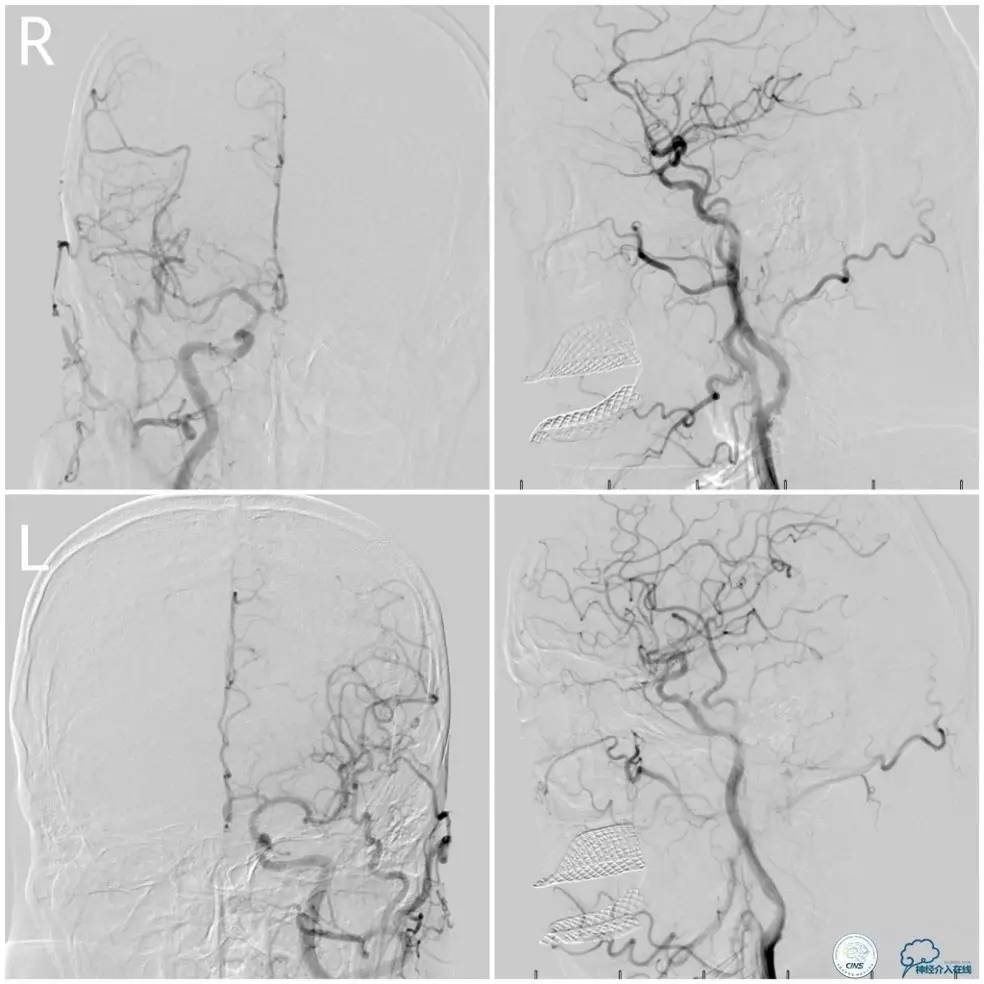

Gateway球囊(1.5mm×15mm)于狭窄段扩张后放置Wingspan支架(2.5 mm×15mm),撤出微导丝后造影,局部狭窄率50%,支架内中远段见细小充盈缺损,考虑急性血栓形成,予以欣维宁5ml动脉内缓慢注射未见好转(图14)。

图14

遂再次将Transend微导丝送至右大脑后动脉P1段,使用Gateway球囊(2.0mm×15mm)于支架最狭窄处后扩张(图15)。

图15

其后造影显示支架贴壁良好,远端血管显影好,前向血流TICI3级(图16)。

图16

缓慢回撤6F导引导管至锁骨下动脉,造影显示右椎V1段支架无移位,前向血流正常(图17)。

图17

2. 本例在近端支架释放完毕后,采用球囊辅助技术顺利的将导引导管越过支架。